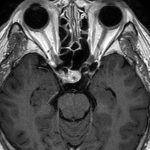

498

'23年12月

20代

下垂体卒中

頭蓋内腫瘍摘出術

No.’23_132 手術前1

No.’23_132 手術前2